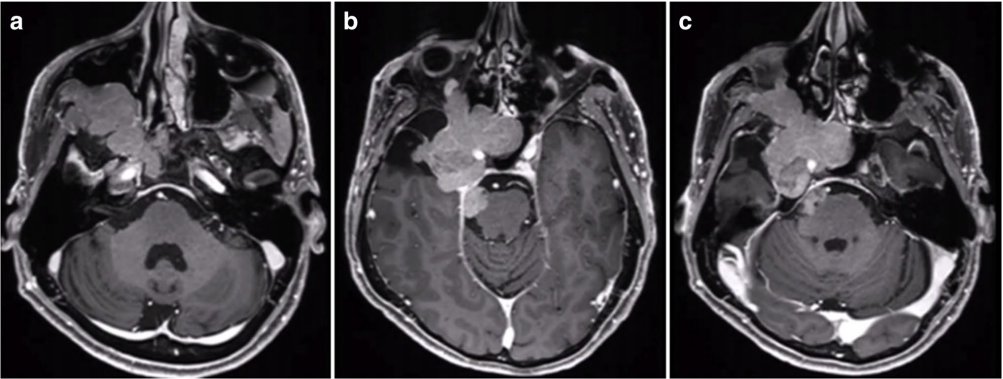

53岁男性患者,7年前在外院手术切除2级脑膜瘤。因出现三叉神经V1、V2区麻木,V3感觉迟钝入院。MRI见巨大脑膜瘤复发侵犯右侧海绵窦、眶顶、SphS、PPF和ITF并通过Meckel’s腔(MC)延伸至小脑桥脑角(CPA)(图 a-c)。

采用原额颞入路,显微镜+神经内镜-“双镜联合”,术后MRI显示肿瘤全切除。